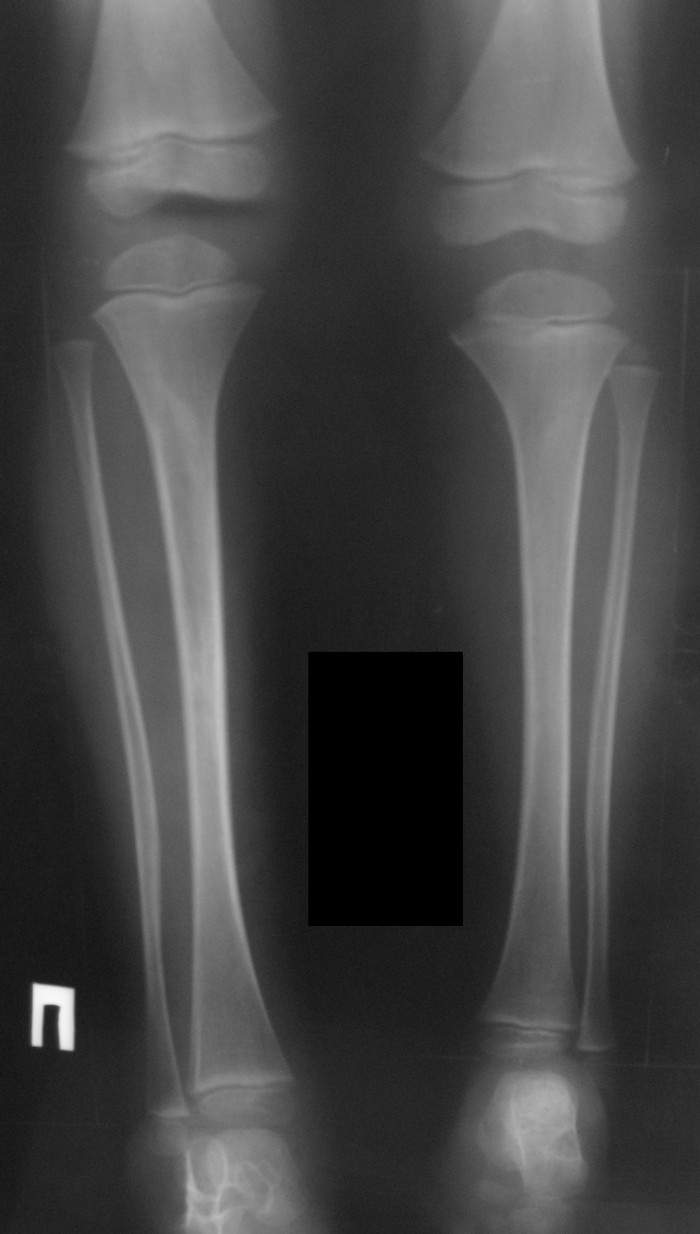

Ребёнок 4 года с подтверждённым диагнозом нейрофиброматоза и удлинением голени. Ребёнок 4 года с подтверждённым диагнозом нейрофиброматоза и удлинением голени. На настоящий момент имеется удлинение и увеличение в размерах правой голени и стопы относительно левой конечности до 5 см. Коррекция диспропорции ног стельками в связи со значительной величиной укорочения уже затруднительна, в связи с чем планируем оперативное лечение. Вопрос возник относительно того, что делать - удлинять здоровую конечность, либо укорачивать увеличенную? С одной стороны, укорочение технически проще, но имеет свои недостатки - слабость мышц вследствие укорочения. С другой стороны: удлинение здоровой конечности - длительный срок аппаратной дистракции и фиксации со всеми вытекающими, необходимость "лечить здоровую ногу"...Хотелось бы знать мение уважаемых коллег.Заранее спасибо.

Взвесили все "за и против" и остановились на эпифизеодезе. Теперь будем ждать результатов.